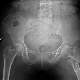

hocam sağkalça eklemimdeki ağrılar için esk. ogü. tıp fak. ne müracat ettim. yapılan tetkikler sonucunda kireçlenme ve eklemde bozukluk tesbit ettiler. Ameliyatla düzelemiyeceğine total kalça protezine karar verdiler.Yaşımın genç olaması sebebiyle (47) bunun da çok iyi bir çözüm olmadığını belirttiler. Ameliyat olmadım.Ben de başka tedavilerin mümkün olup olamıyacağını öğrenmek istiyorum. İlgilenir seniz mr sonuçlarını göndere bilirim.Ümitederim benim derdimin de bir çaresi var dır.Çok teşekkür ederim.

Eklem kıkırdağınız tümüyle aşınmadı ise ve daralma yok ise artroskopik tedavi yapılabilir ancak kıkırdak aşınmış ise eklem protezi ya da yüzeyl değiştirme ameliyatları en uygun çözümdür. Geçmiş olsun